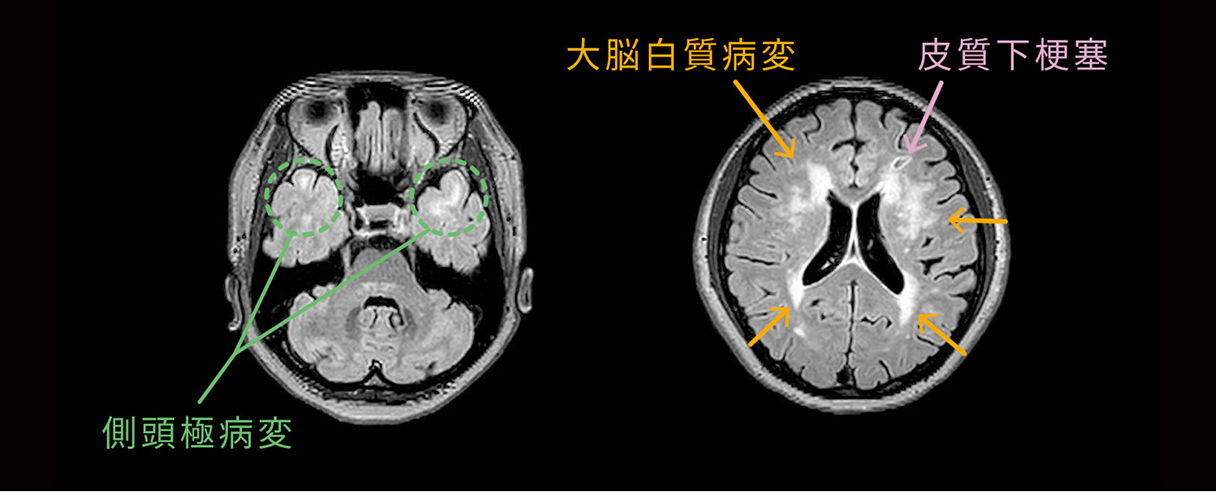

脳の検査(MRI)でみられる特徴

― 診断の手がかり

CADASILでは、MRIで脳梗塞の結果として生じる空洞(ラクナ)や、白質病変と呼ばれるT2強調画像やFLAIR画像の高信号域が認められることが多く、これらが診断の手がかりになります。

特に、側頭極 と呼ばれる側頭葉前方の白質に高信号域が認められた場合、CADASILが疑われることが多いです。しかし、側頭極に病変が見られないCADASILの患者さんも多くいらっしゃいます。